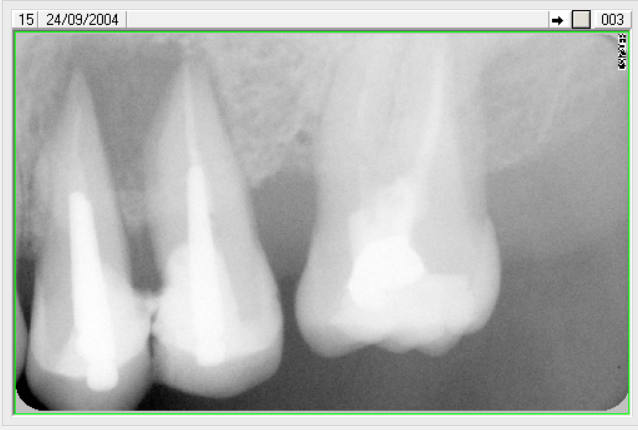

Suite a la demande de HODINA:

j ai retrouvé un autre cas d'extraction réimplantation .

extraction 2004

controle 2006

je peux convoquer la patiente pour radio si vous voulez voir 2014. ce qui est sur ç est que les dents sont tjs en bouche.

d'ailleur il faudrait que je le fasse car j avais scellé les 2 coiffes solidarisées au temp-bond.Je n avais pas pu les enlever par la suite.erreur.

2004 eic2ap - Eugenol

2006 beu3qo - Eugenol